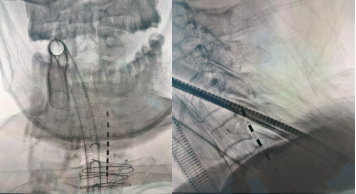

经综合评估,顿志平向家属提出可先行植入测试电极进行脊髓电刺激,若治疗效果理想,后期再置入永久性脊髓电刺激器,以助改善患者肢体运动功能、提高生活质量,患者家属慎重考虑后接受手术。术中,顿志平、副主任医师王小飞及护理、麻醉团队密切协作,顺利完成手术,X线影像确认测试电极位置理想。术后次日开始进行脊髓电刺激治疗,现已测试治疗1周,患者上肢运动及语言功能明显改善,且便秘、体位性低血压等自主神经功能障碍亦有一定的改善。患者术后恢复良好,拟择期进一步为患者置入永久性脊髓电刺激器。

术中X线影像确认测试电极位置准确